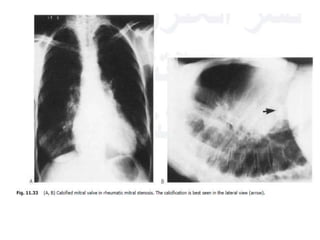

• Severe and longstanding mitral stenosis:

calcification of the valve can develop.

• Best visualised in the lateral position but can

sometimes be visualised in the PA projection if

the film is penetrated.

• This calcification needs to be differentiated

from the far more common C- or J-shaped

calcification that occurs in the valve annulus.